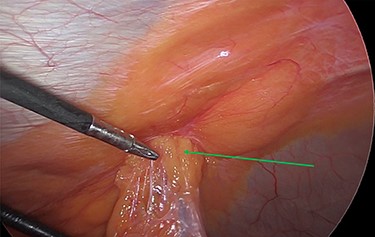

The viable omentum was reduced into the peritoneal cavity. Two lipomas were then observed attached to the parietal peritoneum (Figs 3 and 4). The lipomas were also reduced into the peritoneal cavity from within the hernia sac. Each one was 2 cm in diameter based on laparoscopic visualization using the 1 cm markings on a suction irrigation device.

The two peritoneal lipomas (green arrows) and the visible umbilical hernia neck (blue circle). Intracorporeal suturing of the hernia neck (green arrow) and closure of the hernial defect.